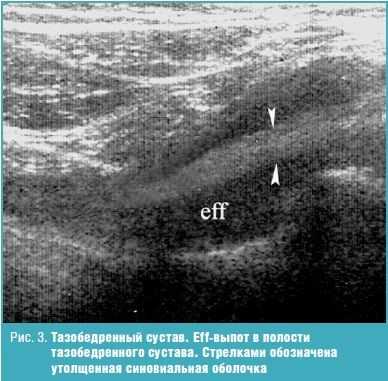

Результаты проведенного исследования показали (табл.), что у больных ПсА выявляется поражение всех анатомических структур сустава с разнообразной ультразвуковой картиной. Наиболее распространенными изменениями в суставах были увеличение количества внутрисуставной жидкости и пролиферация синовиальной оболочки. Появление жидкости в суставах определялось у подавляющего числа пациентов (90%), и только у 10% наблюдаемых детей жидкость в суставной полости отсутствовала. В нашем исследовании преобладал однородный выпот в полость сустава (82%). Неоднородность структуры (18%) была обусловлена выявлением на фоне анэхогенного содержимого гиперэхогенных включений (фибрин). Увеличение синовиальной оболочки в виде диффузного утолщения выявлено в 90% суставов (рис. 1-3). В 11,5% случаях имело место истончение хряща (выявлено у пациентов с длительностью заболевания от 5 лет и более), которое в ряде наблюдений сопровождалось изменением контуров в виде неровности и нечеткости, а в ряде случаев — изменением нормальной эхоструктуры.